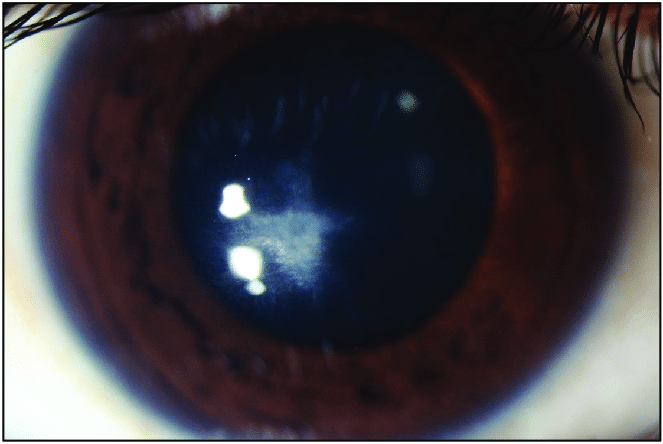

Fleischer Ring이란, 튀어나온 원추부분을 둘러싸고 철분이 각막에 침착되는 것입니다.

원추의 바닥부에 원추바닥의 가장자리를 따라서 흔히 관찰되는데,

부분적인 혹은 완전한 원형의 선이 나타납니다.

원추 주변부경계의 지표가되는데,

바닥상피에 침착된 혈철소(hemosiderin)으로 인해서 형성된것으로,

돌출이 질행될수록 점점더 고리는 더 진하게 침착되면서, 가늘어지고, 완전한 원형을 이루게됩니다.